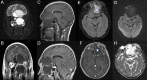

Juvenile psammomatoid ossifying fibroma (JPOF) is a rare, benign type of ossifying fibroma. JPOFs predominantly present as rapidly growing masses with a high recurrence rate. We report a 40-year-old male patient who suffered from a large tumor with multiple invasions into the paranasal sinuses. Total excision was performed, and significant relief of clinical symptoms was recorded after 4 months of follow-up. Multi-departmental management involving radiologists, neurology surgeons, craniofacial surgeons, pathologists, and otolaryngologists is vital for JPOF treatment. First-line treatment options include total or partial resection, depending on the patient's condition.